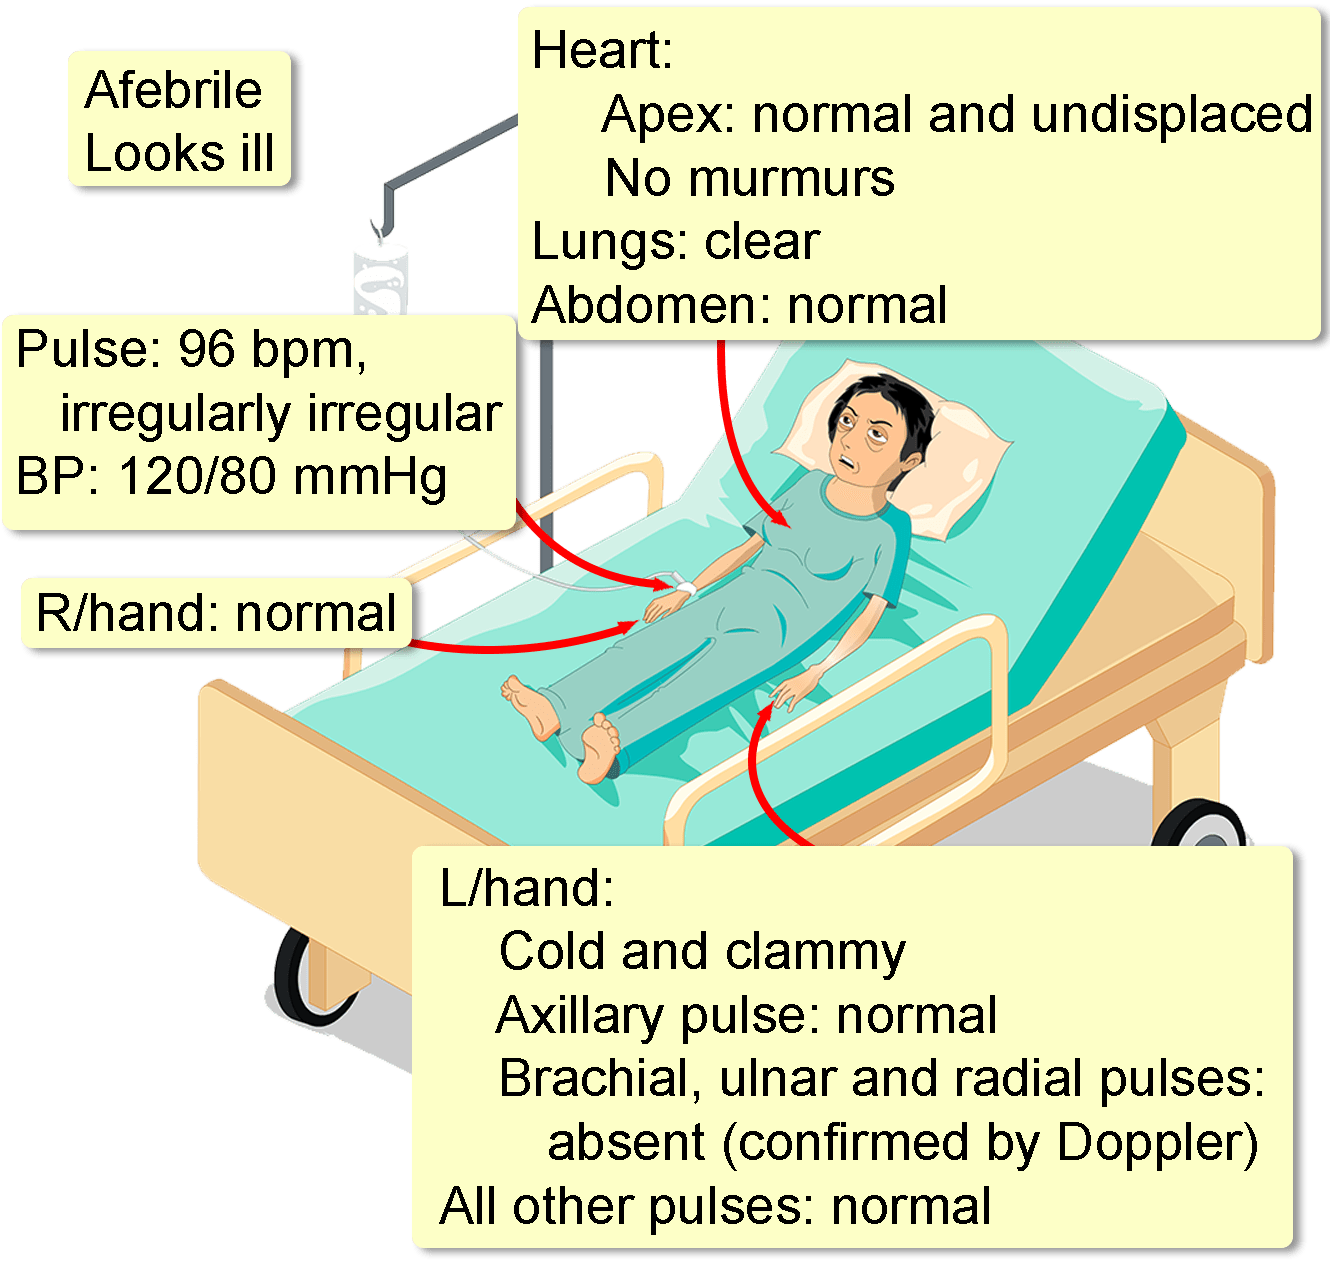

Ischemia is a vascular disease involving an interruption in the arterial blood supply to a tissue organ or extremity that if untreated can lead to tissue death It can be caused by embolism thrombosis of an atherosclerotic artery or trauma Venous problems like venous outflow obstruction and low flow states can cause acute arterial ischemia Ischemia is a condition in which the blood vessels become blocked and blood flow is stopped or reduced When blood flow is diminished to a body part that body part also does not receive adequate oxygen legs critical limb ischemia a form of peripheral artery disease and intestines acute mesenteric ischemia or bowel ischemia

Ischemia is an insufficient supply of blood to an organ usually due to a blocked artery Myocardial ischemia is an intermediate condition in coronary artery disease during which the heart tissue is slowly or suddenly starved of oxygen and other nutrients Ischemia means that there is a reduced blood and oxygen supply to a certain part of the body Locations in the body this condition can affect include the heart intestines brain and limbs Ischemia can happen due to structural or functional problems in the heart but it can have a variety of causes

Acute Limb Ischemia